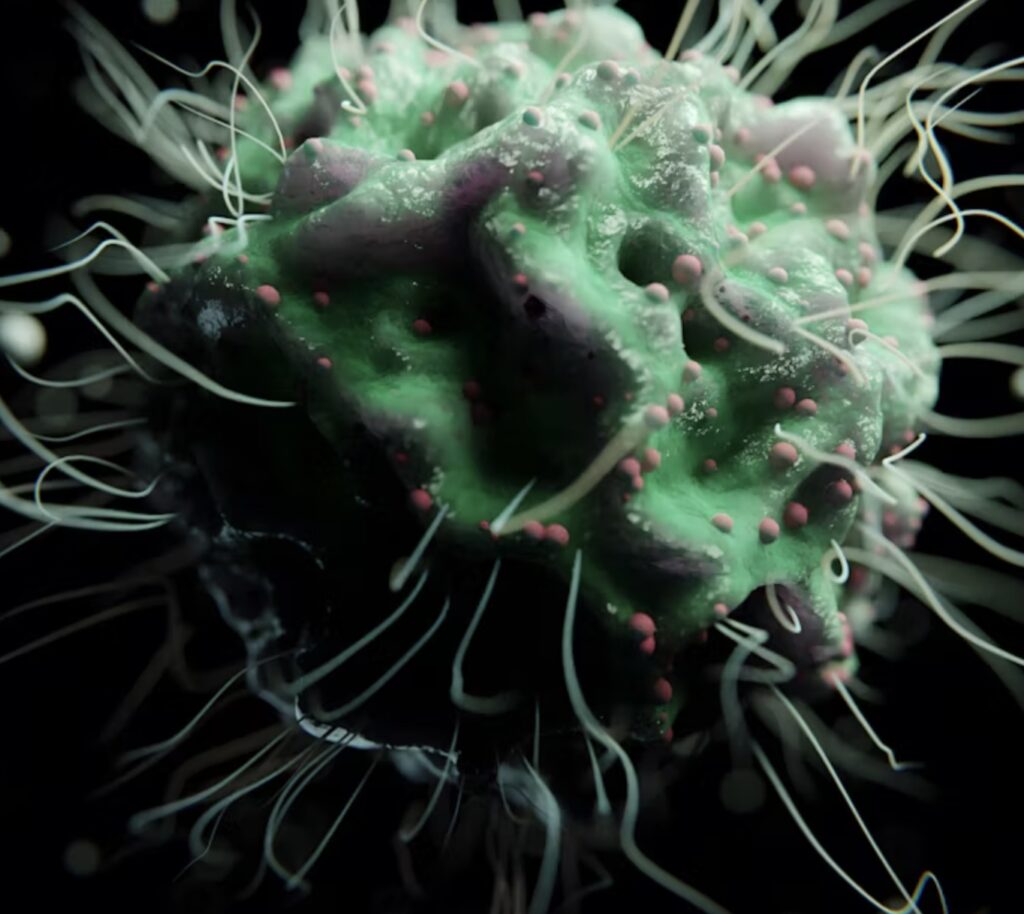

You might think of a cavity as a personal dental problem, something that happens...

You might think of a cavity as a personal dental problem, something that happens to your own teeth because of your diet or brushing habits. But what if we told you that the bacteria that cause cavities can actually spread from person to person? It’s a surprising reality. While you can’t "catch" a physical cavity like you would a cold or the flu, the microscopic organisms responsible for them can absolutely be shared. A cavity is, at its core, a bacterial infection, and the primary culprit is a bacterium known as Streptococcus mutans. These tiny organisms thrive in our mouths, feeding on the sugars and carbs we consume. In return, they produce acids that gradually erode tooth enamel, creating the tiny pits that eventually become cavities.

This is why it's so important to understand how these bacteria are transmitted. The primary method is through saliva, which means sharing utensils, cups, and even a simple kiss can transfer these cavity causing microbes. Parents are often the unwitting carriers, unknowingly passing these bacteria to their infants and young children by blowing on food to cool it or cleaning a dropped pacifier with their mouth. Children don't begin life with these specific bacteria in their mouths; they typically acquire them from their caregivers, making early childhood a particularly critical time for prevention.

Of course, being exposed to these bacteria doesn't automatically mean you'll get a cavity. Whether a cavity develops depends on a combination of factors. Your daily oral hygiene habits like regular brushing with fluoride toothpaste and flossing are your first and best defense. Your diet also plays a crucial role; the less sugar you consume, the less fuel you provide for the bacteria to create harmful acids.

Additionally, genetics and natural saliva flow can influence your susceptibility, as a healthy flow of saliva helps neutralize acids and wash away food particles.

Knowing this, you can take simple but powerful steps to protect your smile and the smiles of those you love. The most effective way to prevent the spread is to avoid sharing don’t share toothbrushes, cups, or eating utensils. Maintain excellent personal oral hygiene with consistent brushing and flossing, and be mindful of your diet to limit sugar intake. For parents, being aware of how you handle your child’s food and pacifiers can make a world of difference in their long-term dental health.

Understanding that a cavity is a bacterial infection is the first step toward better oral care, allowing you to be proactive in preventing the spread and keeping your teeth healthy and strong.